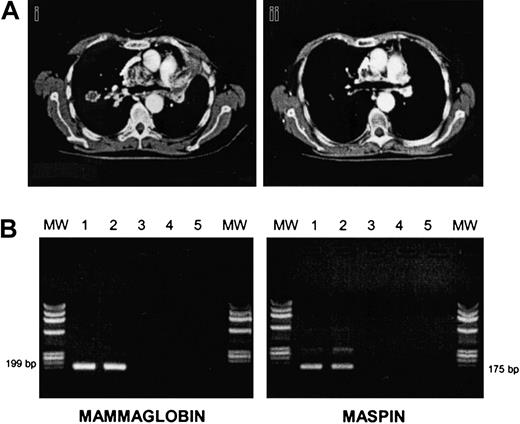

There were 3 of 7 RCC patients who progressed soon after the transplantation (median time, 61 days). There were 4 patients who responded after CSA withdrawal; patient no. 7 relapsed but eventually responded again to DLIs plus IFNα (Figure1A). The other 2 RCC patients had stable disease, and patient no. 11 (papillary RCC) died of progressive disease 10 days after the first DLI. In all BC patients, disease progressed at a median of 69 days after the transplantation (range, 41-232 days). In order to induce a GVT effect, all patients (except patient no. 5 who died of progressive disease at day +109) received escalating doses of DLIs, at a median of 51 days after disease progression (range, 12-78). We observed 2 partial responses (patients no. 3 and no. 6): one after a single-dose DLI, the other after 2 infusions followed by IFNα. Patient no. 3 had an extensive skin and lymph node involvement before allografting that partially regressed along with a grade II acute GVHD developing after DLI. Patient no. 6 was unique since she had bone marrow involved by disease before and after allografting, and bone lytic metastases. BC cells were still present in the marrow before DLI, as assessed by morphology, cytokeratine immunohistochemistry, and by RT-PCR for maspin and mammaglobin genes. After DLI plus IFNα she developed a grade II acute GVHD, and then marrow samples became PCR-negative for maspin and mammaglobin gene expression (Figure 1B). We and others have previously shown that RT-PCR for maspin and mammaglobin is a sensitive and specific assay for detecting occult BC cells.13 This finding suggests a GVT effect at the marrow level.

(A) CT thorax scan of patient no. 7 before (i) and after (ii) DLI plus IFNα. (B) RT-PCR analysis of mammaglobin and maspin expression in bone marrow cells of patient no. 6 before and after DLI. Bone marrow mononuclear cells were analyzed for mammaglobin and maspin expression preallograft (lane 1), before DLI (lane 2), and after DLI (lane 3), respectively. Lane 4: negative control; lane 5: no DNA. MW indicates molecular weight marker.